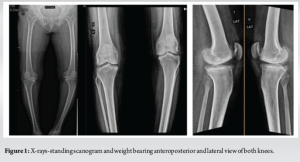

We report a 65-year-old woman (IP No2309804) with 2 years of bilateral knee pain and swelling, worsened by activity. She experienced night pain, cracking sounds, and reduced mobility due to advanced bilateral osteoarthritis (stage 4) with varus and fixed flexion deformity (FFD) (Fig. 1).Sequential bilateral robotic-assisted TKA was recommended.

We commenced robotic-assisted TKA at our institution utilizing the Curexo-Meril Cuvis system, a fully automated robotic platform from Korea, in September 2023. This image-based ,implant specific system utilizes computed tomography scans and mill technology, featuring a pre-cut gap check that assists in addressing gaps and achieving soft tissue balance. It allows for the adjustment of implant positioning without the need for soft tissue release or excision of osteophytes. This marks our 25th case, highlighting our initial experience amid a significant learning curve. After obtaining physical fitness, the patient undergone surgery on December 08, 2023. The procedure adhered to standard robotic-assisted surgical protocols, employing kinematic alignment alongside pre- and post-cut gap assessments. Optimal balance was maintained throughout the range of motion, resulting in satisfactory patellar tracking. We utilized the Destinee Maxx-Meril cobalt-chromium-based multiradii curve femoral implant (size D), along with a titanium tibial tray (size 3) featuring an 11 mm high-flexion design polyethylene insert on both sides (Fig. 2). Intraoperative navigation confirmed satisfactory alignment, and post-operative radiographs corroborated this. The post-operative period proceeded without complications. The patient was assisted in walking with a walker 8 h after surgery. Standard post-operative protocols for antibiotic administration and deep vein thrombosis prevention were implemented. On the 5th day following surgery, the patient was discharged with detailed instructions for rehabilitation. The patient returned on the 14th post-operative day for suture removal, showing proper wound healing and no signs of infection. A check x-ray revealed satisfactory implant alignment (Fig. 3). The patient was then referred to the physiotherapy department to begin stage 2 and 3 of the rehabilitation program. There is limitation for collection of quantitative data.